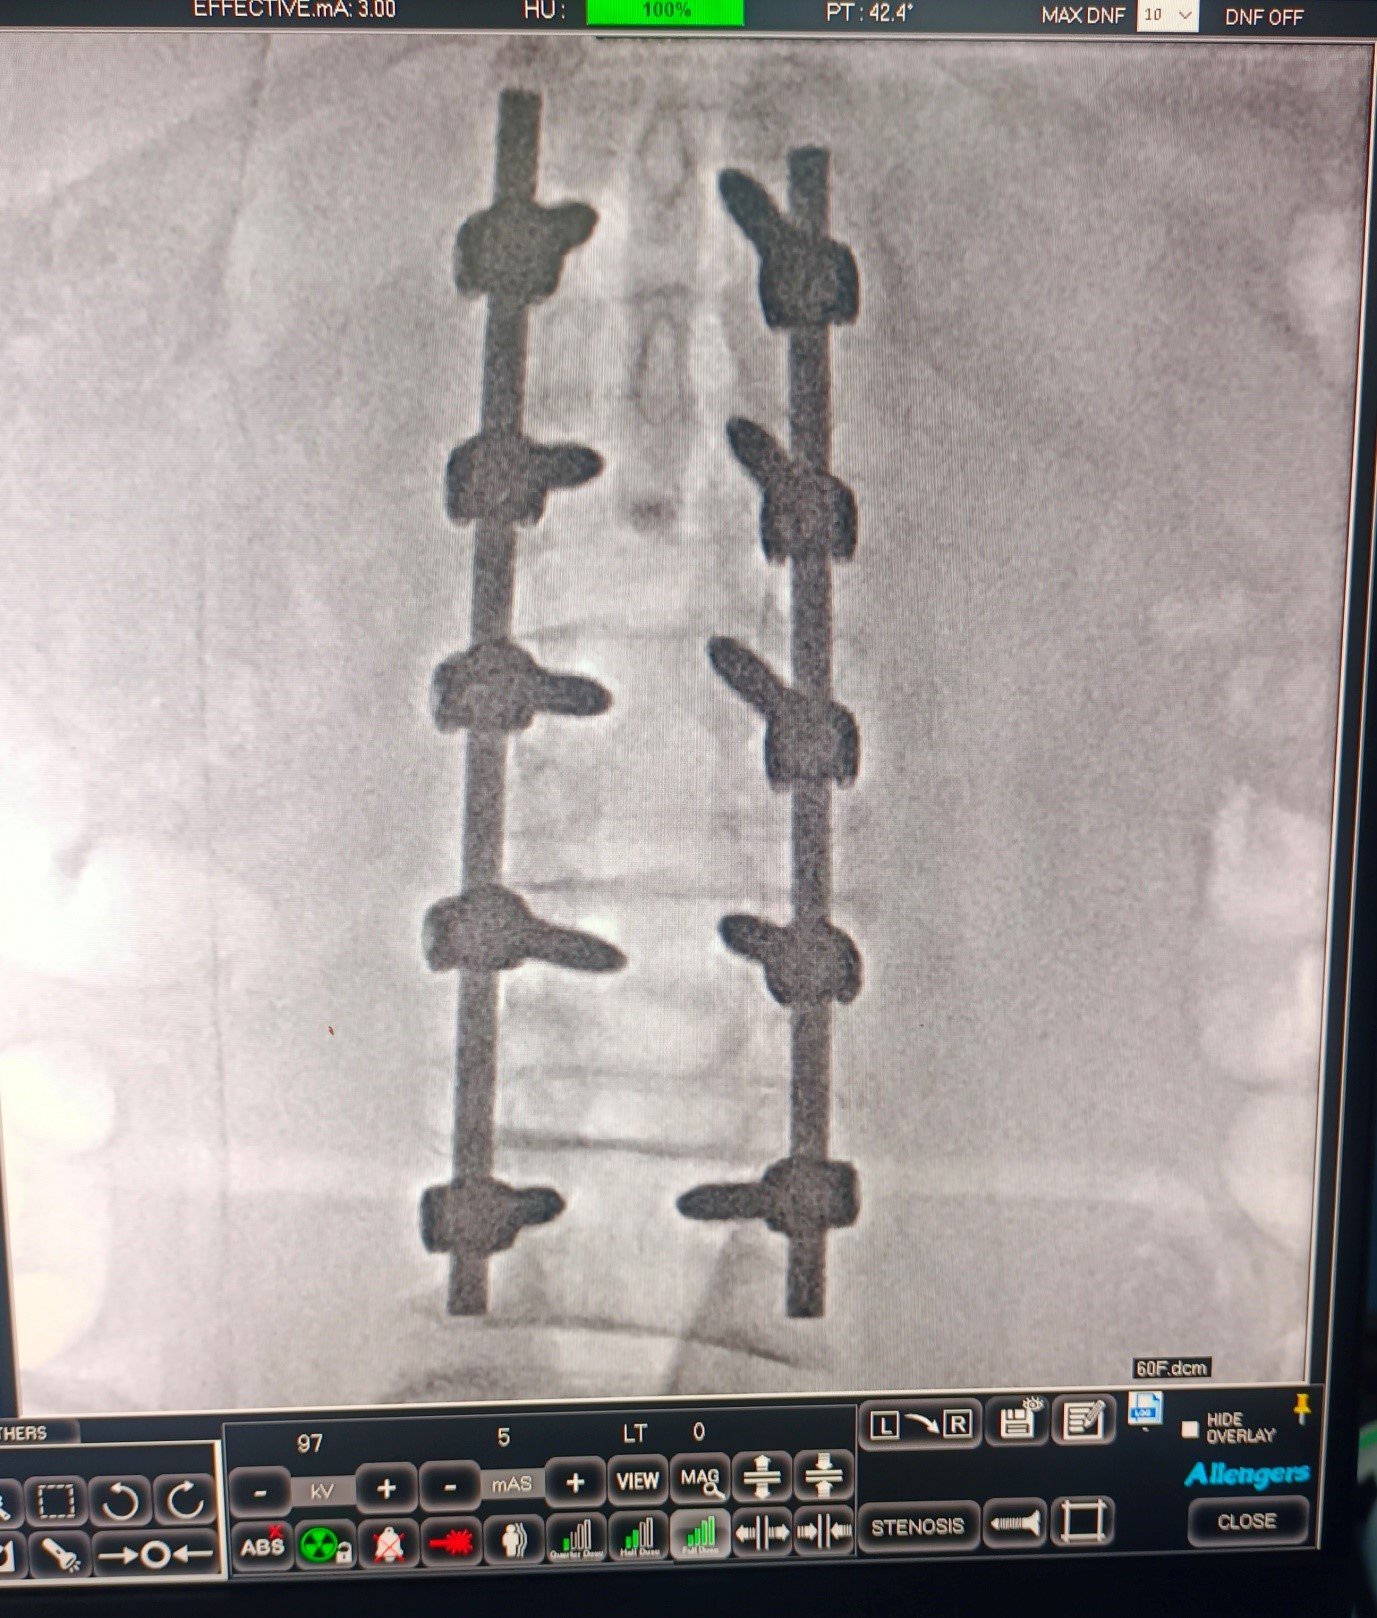

Cervical Disc Prolapse with Spinal Cord Compression

Special Cases Cervical Disc Prolapse with Spinal Cord Compression Condition:Cervical disc prolapse in which the herniated disc compresses the nerve roots and spinal cord, often associated with spinal cord edema. Symptoms:Neck pain, numbness in hands, weakness, difficulty in walking, and coordination problems. Treatment:Anterior Cervical Discectomy and Fusion (ACDF) – The…